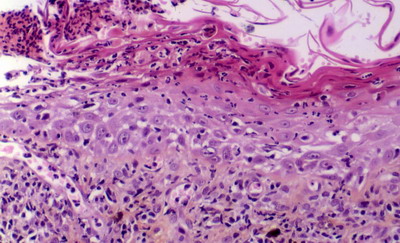

“On remarque en surface un épiderme acanthosique et relativement spongiotique. Par endroits apparaissent des exulcérations d’assez grande taille. Celle-ci sont recouvertes par des croûtes massivement infiltrées par des polynucléaires dégénérés (+ des acanthocytes). L’attention est ensuite attirée par de nombreuses images de dégénerescence hydropique cantonnées sur la couche basale .

Le derme superficiel fait l’objet d’une infiltration lichénoïde lymphoplasmocytaire. On remarque de plus une incontinence pigmentaire intense.